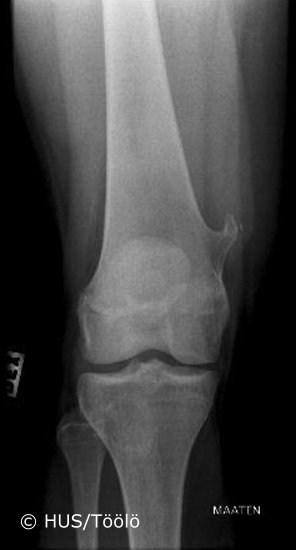

Exostosis in the femur.Osteochondroma (exostosis) is a benignbone tumour. It is found in the metaphyseal regions of the long bones, most commonly in the distal femur, proximal tibia and proximal humerus. An osteochondroma stops growing as the patient's years of growth are over.

Picture: Aarne Kivioja; text: Aarne Kivioja and Minna Laitinen